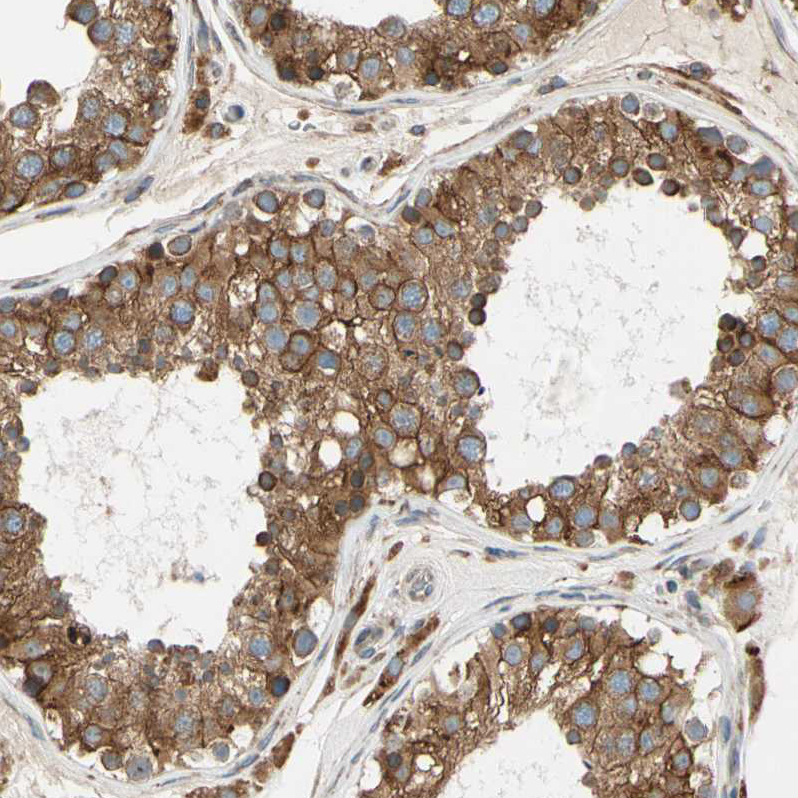

Immunohistochemical staining of human epididymis shows strong granular cytoplasmic positivity in glandular cells.